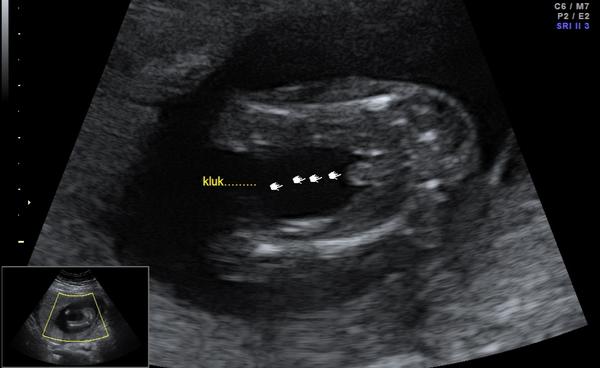

chtěla bych se s vámi poradit, co si myslíte, že čekáme 🙂, určitě máte některé zkušenější oko než my a jelikož jsme od doktorů slyšely obě varianty, ráda se poradím i s vámi, určitě jste takových obrázků už viděly spoustu 🙂. Přikládám foto z UTZ ve 20.týdnu. Moc děkuji!

Holky moc děkuji za reakce 🙂. Mně se to také spíše zdá jako holčička, pan doktor nám ale právě během této kontroly řekl, že tam vidí spíše kluka, což mě dost překvapilo 😃. Je mi jasné, že jistotu budeme mít až po porodu, ale spíš jsme prostě zvědaví 🙂.

Mně to zase přijde víc jako kluk, vpravo je tam něco jako pytlík vedle toho kávového zrna... No těžko říci 😀